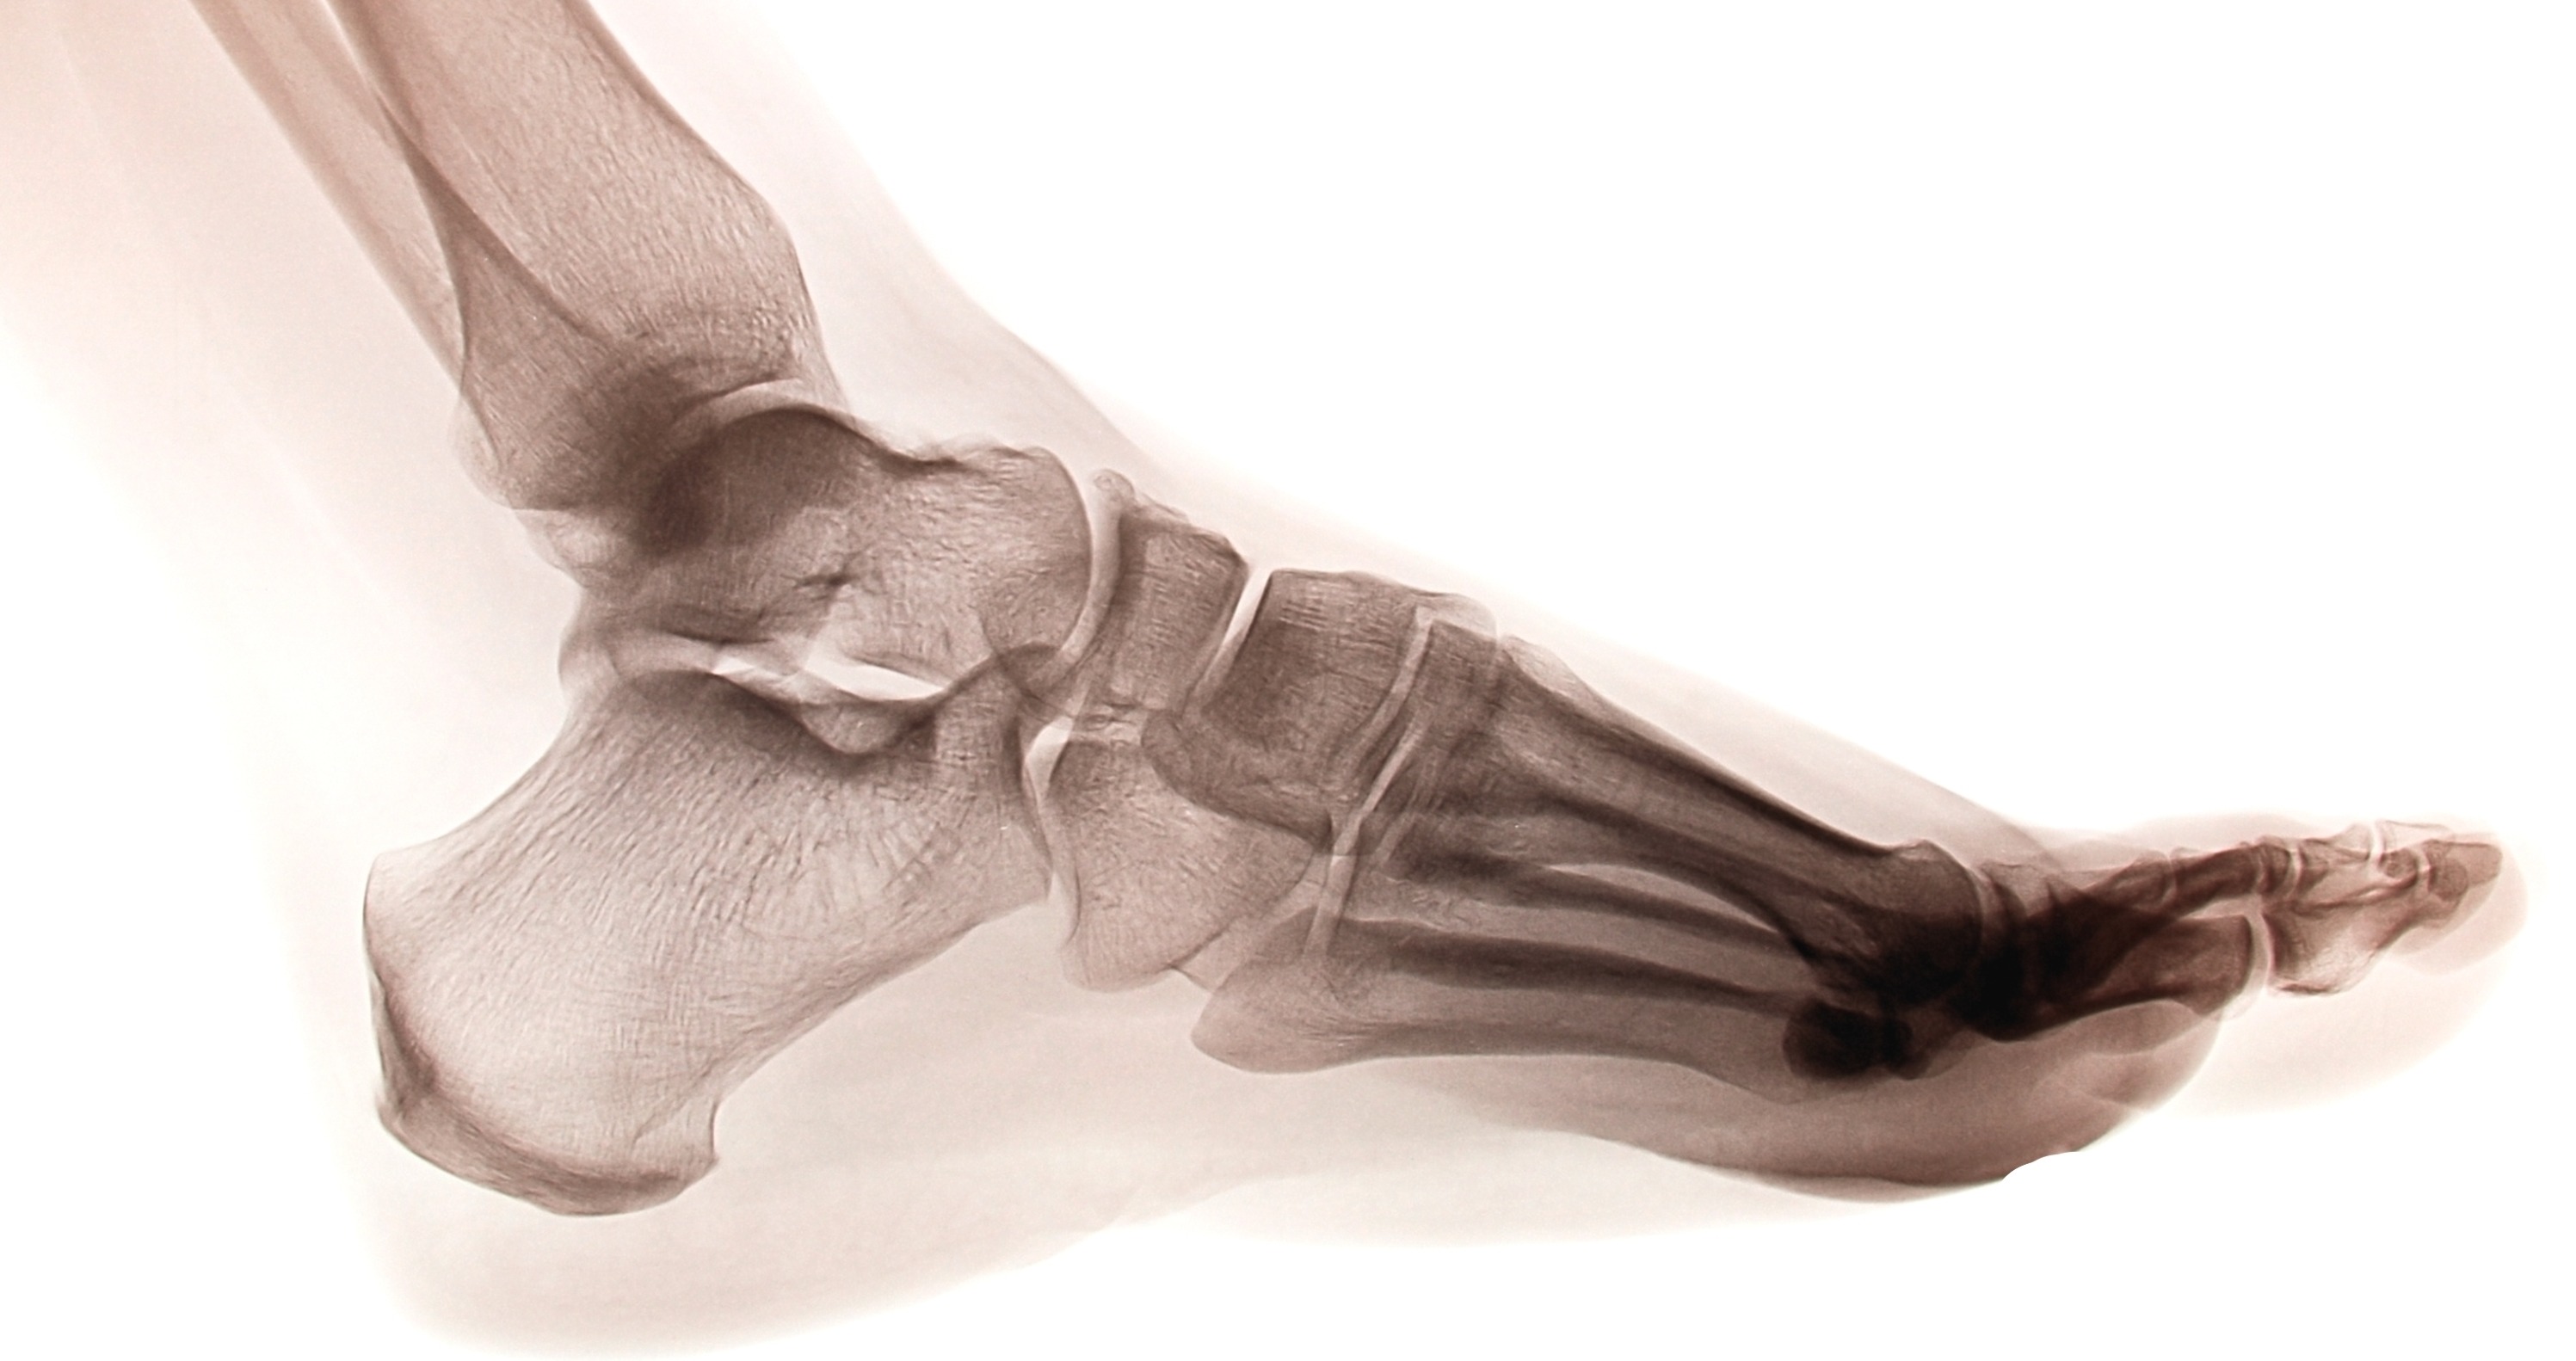

To comprehend the biomechanics of the foot and ankle, you must first understand the intricate structure that enables movement. The foot is divided into three main anatomical regions: the hindfoot, midfoot, and forefoot—each playing a unique role in foot biomechanics.

The hindfoot, located immediately under the ankle joint, forms the posterior foundation of foot biomechanics. This region consists primarily of two crucial tarsal bones:

The hindfoot's biomechanical function centers around the subtalar joint, which allows for inversion and eversion movements crucial for adapting to uneven surfaces and absorbing impact forces.

The midfoot contains five additional tarsal bones that contribute significantly to the biomechanics of the foot:

The junction between the midfoot and hindfoot, known as Chopart's joint, plays a vital role in foot biomechanics by allowing the foot to adapt its shape during different phases of gait.

The forefoot includes the metatarsals, phalanges, and sesamoid bones. The Lisfranc joint, where the midfoot and forefoot meet, is crucial for push-off mechanics during the propulsive phase of gait.

The main players in the biomechanics of the foot and ankle are the tibiotalar joint and the transverse tarsal joint. The tibiotalar joint, otherwise known as the ankle joint, is what allows the foot to move up and down with help from the muscles in the front and back of the leg. The transverse tarsal joint is what helps movement go forward, and aids with shock absorption and heel rise. The tendon attached to the joining helps the bone move, and when it’s not moving (i.e., absorbing shock), it locks.

The biomechanics of the foot and ankle serve as the foundation for all human movement. From the complex coordination of 28 bones and 33 joints to the precise timing of muscle activation patterns, every aspect of foot biomechanics contributes to our ability to move efficiently and effectively.